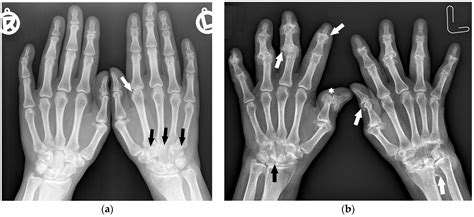

• Monitoring Treatment: For babies undergoing treatment for conditions like juvenile arthritis, X-rays can track the effectiveness of the treatment.

• Congenital Anomalies: Conditions like syndactyly (fused fingers) or polydactyly (extra fingers).

• Infections: Signs of bone infections or osteomyelitis.

• Chronic Conditions: For babies with chronic conditions like juvenile arthritis, to monitor bone health.